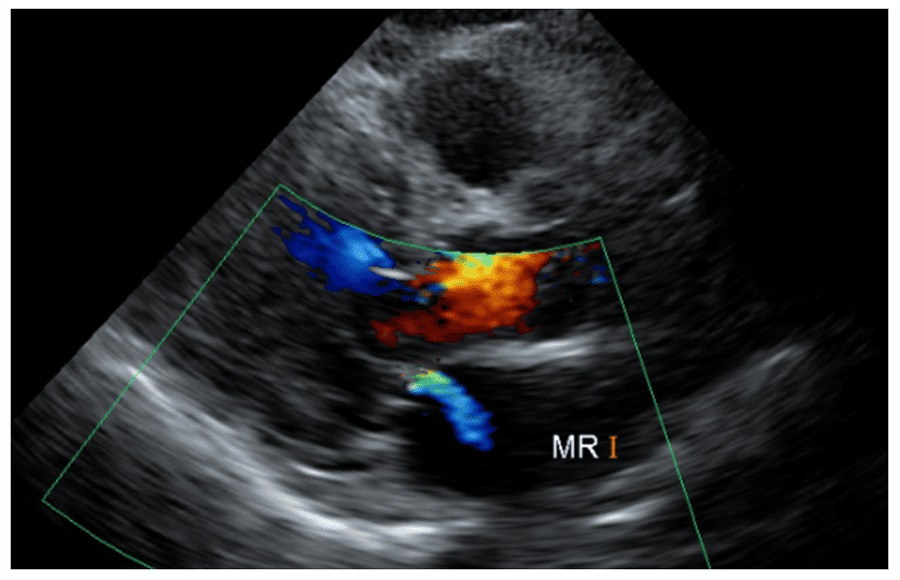

僧帽弁逆流

主な所見

僧帽弁逆流/大動脈弁逆流

心臓の弁が正常に閉まらないことで血液が逆流している状態です。血液の逆流が軽度な場合、症状を自覚することはほぼありませんが、中等度~高度になると息切れや動悸、呼吸困難などがみられることがあります。原因として先天的なものや後天的なものがあり、加齢が原因となることもあります。